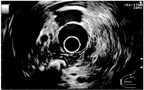

可见胰腺区伴声影的高回声病灶、胰管形态变化等。因其灵敏度不高,仅作为CP的初筛检查。此外,对于假性囊肿等CP并发症具有一定的诊断意义。

| 影像学特征性表现 | 下列任何一项:①胰管结石;②分布于整个胰腺的多发钙化;③ ERCP显示主胰管不规则扩张和全胰腺散在不同程度的分支胰管不规则扩张;④ ERCP显示主胰管完全或部分梗阻(胰管结石或蛋白栓),伴上游主胰管和分支胰管不规则扩张 | 下列任何一项:① MRCP显示主胰管不规则扩张和全胰散在不同程度的分支胰管不规则扩张;② ERCP显示全胰腺散在不同程度分支胰管扩张,或单纯主胰管不规则扩张,或存在蛋白栓;③ CT检查示主胰管全程不规则扩张伴胰腺形态不规则改变;④超声或超声内镜显示胰腺内高回声病变(考虑结石或蛋白栓),或胰管不规则扩张伴胰腺形态不规则改变 |